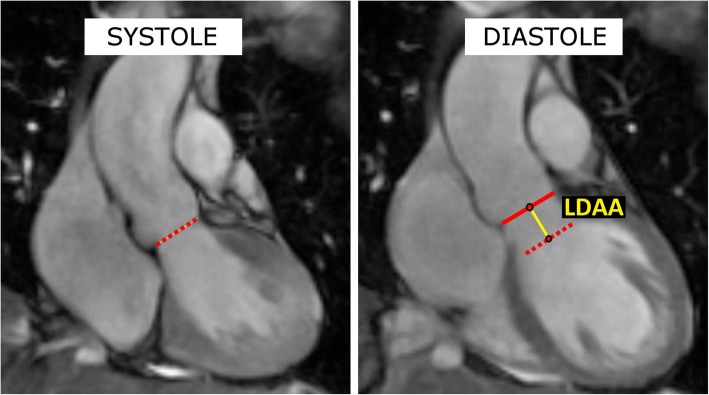

The CMR images were analyzed in the coronal cine-MRI view. The maximum distance to which the ventriculo-aortic junction (VAJ) was pulled by the contracting heart was measured (LDAA – longitudinal displacement of the aortic annulus). First, the position of the VAJ was established in the maximum systole and diastole, then the distance between the mid-points of the VAJ in systole and diastole was measured. Moreover, the maximum dimensions of the aortic root and the ascending aorta were assessed. The methodology of the measurements is presented in Fig. 1.

Fig. 1.

The measurements taken from the coronal cine-MRI sequences. Left (systole): red dotted line - the position of the ventriculo-aortic junction (VAJ) in systole. Right (diastole): red dotted line - the position of the ventriculo-aortic junction (VAJ) in systole, red line - position of the ventriculo-aortic junction (VAJ) in diastole; yellow line – the longitudinal displacement of the aortic annulus (LDAA)- the line links the mid-points of the VAJ in systole and diastole